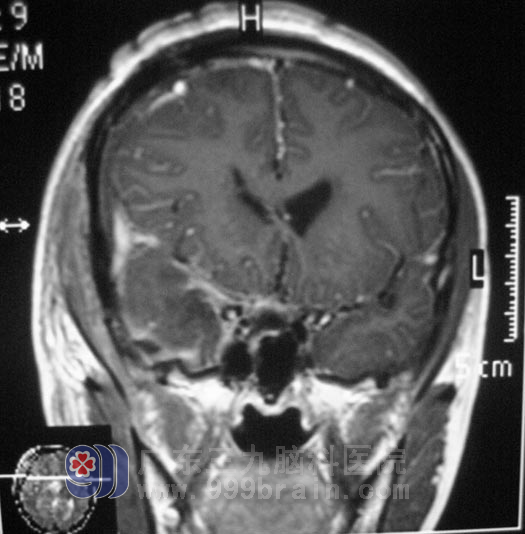

小敏,两月前出现反复阵发性头痛,伴有恶心、呕吐,偶有头晕,母亲带着她到当地医院就诊,颅脑MR检查提示:三脑室占位性病变。

完善相关检查后,5月10日,由鲁明主任主刀,在全麻下行三脑室占位性病变切除术,术中见肿瘤呈灰白色,边缘质硬,中心部位质软,血供一般,呈鱼肉样,在显微镜下予肿瘤切除,手术过程顺利。手术后小敏的情况一天一天好转,现已经出院在家。术后病理结果为:(第三脑室)毛细胞型星形细胞瘤,WHO I级。